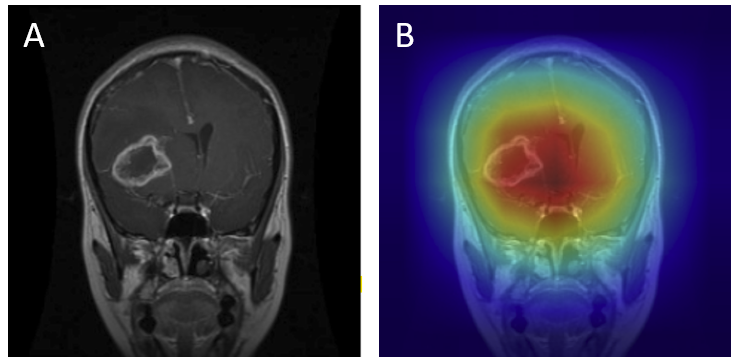

Grad-CAM visualizations of correctly classified cases confirm that the model focuses on regions consistent with radiological expectations. In these overlays, warmer colors (red and orange) highlight the areas where the network places the greatest emphasis during prediction, while cooler colors (blue) correspond to regions with minimal contribution. This distinction allows direct inspection of whether the model bases its decision on clinically relevant cues.

For gliomas, the heatmaps align with intra-axial lesions exhibiting infiltrative margins (Figure 8). Meningiomas are accurately identified at dural or peripheral attachment sites, consistent with their extra-axial presentation (Figure 9). Pituitary adenomas are localized to the sella turcica with concentrated red activation at the lesion boundaries (Figure 10). Finally, in no tumor cases, the activation maps remain diffuse or midline-focused without strong hotspots, consistent with normal anatomy (Figure 11). The correspondence between the model's attention and radiological landmarks indicates that the network is learning meaningful diagnostic features rather than relying on spurious correlations.

Figure 8: Glioma — original (A) vs. Grad-CAM (B), correct model prediction.

Glioma Correct